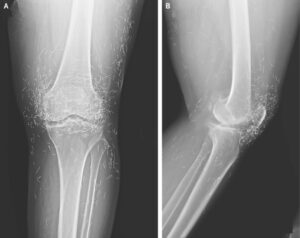

Acupuncture, a centuries-old alternative treatment, involves inserting needles into the body at specific points to relieve pain or treat illnesses. In this case, the needles— presumably made of gold — were intentionally left in her knees for continued stimulation.

He also warned that embedded needles can complicate X-ray readings. “The needles may obscure some of the anatomy,” Guermazi said in 2013.

Even more concerning, needles left in the body can make future medical imaging dangerous. “The patient can’t go into an MRI because needles left in the body may move, and damage an artery,” Guermazi added.